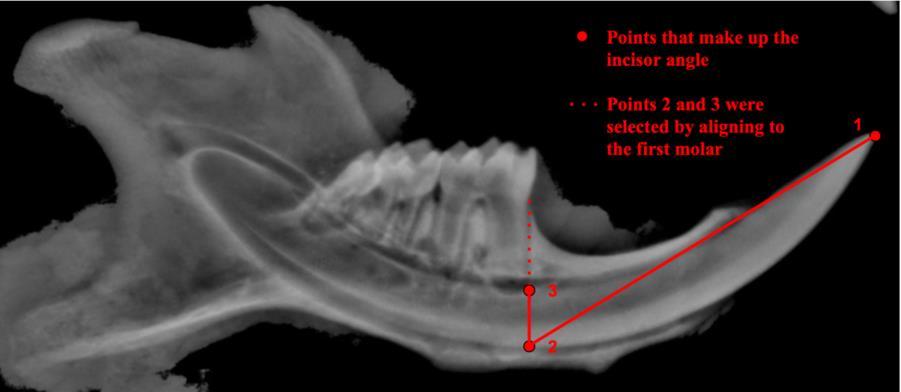

Mandibular Measurements

Measurements of mandibular lengths included: (1) incisor tip to molar 1, (2) incisor tip to temporomandibular joint (TMJ), and (3) incisor tip to angular process (Fig 2), in addition to the incisor curvature, as detailed in Figure 3 Measurements were carried out using ImageJ software. The measurements of these mandibular parameters and the incisor angle are reflections of whether the mandible is hypoplastic in Gnas E1+/- mice compared to that of wild-type mice.

Figure 2 Mandibular lengths used for measurements Three distinct lengths were measured including (1) incisor tip to first molar, (2) incisor tip to TMJ, and (3) incisor tip to angular process.

Figure 3. Calculating the incisor angle. Incisor angles were measured starting from the incisor tip, going down to the base of the alveolar bone, and then tracing directly upward to the base of the first molar as indicated in red.